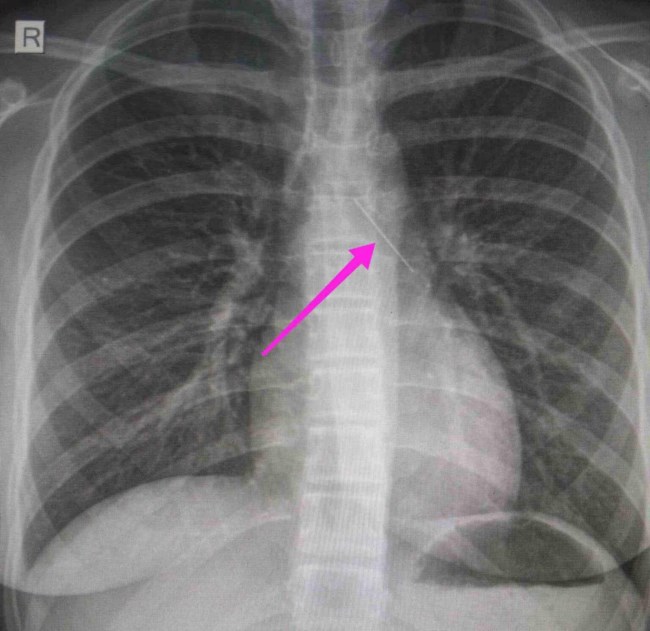

Από την απεικονιστική διερεύνηση που πραγματοποιήθηκε με ακτινογραφία θώρακος αρχικά και ακολούθως με αξονική τομογραφία θώρακος, διαπιστώθηκε η ύπαρξη αιχμηρού μεταλλικού ξένου σώματος στην αναπνευστική οδό (αριστερός κύριος βρόγχος) και όχι στην πεπτική οδό, αναφέρει η ανακοίνωση του νοσοκομείου, στα μέσα κοινωνικής δικτύωσης.

"Χθες 30/1/2022 στις 16:00 στο Τ.Ε.Π. του ΓΝΘ Ιπποκράτειο, προσήλθε ανήλικη συνοδευόμενη από τους γονείς της, μετά από αναφερόμενη κατάποση ξένου σώματος (καρφίτσα). Από την απεικονιστική διερεύνηση που πραγματοποιήθηκε με ακτινογραφία θώρακος αρχικά και ακολούθως με αξονική τομογραφία θώρακος, διαπιστώθηκε η ύπαρξη αιχμηρού μεταλλικού ξένου σώματος στην αναπνευστική οδό (αριστερός κύριος βρόγχος) και όχι στην πεπτική οδό.

Κατά την βρογχοσκόπηση διαπιστώθηκε η μετακίνηση και ενσφήνωση του ξένου σώματος στον δεξιό κύριο βρόγχο. Μετά οπό εργώδεις προσπάθειες ολοκληρώθηκε με επιτυχία η αφαίρεση αυτού. Η ασθενής ανένηψε πλήρως εντός της χειρουργικής αίθουσας. Η ασθενής μεταφέρθηκε για παρακολούθηση και νοσηλεία στη Γ’ Παιδιατρική Κλινική.